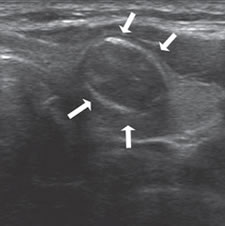

El patrón de calcificación periférica anular se consideró alguna vez que representaba un hallazgo benigno, pero un estudio demostró asociación con malignidad en 18,5% de los casos17. En ese estudio hubo una tendencia hacia un mayor riesgo de malignidad si el patrón periférico de calcificación era discontinuo (Figura 9) y un menor riesgo de malignidad si el patrón periférico de calcificación era liso y curvilíneo, en forma de cáscara de huevo (Figura 10).

Figura 9. Cáncer papilar, de forma redondeada, de 30 mm de diámetro,

hipoecogénico, con microcalcificaciones periféricas y discontinuas

(flechas). En el aspecto posterior las microcalcificaciones

forman un contorno lineal (flecha abierta).